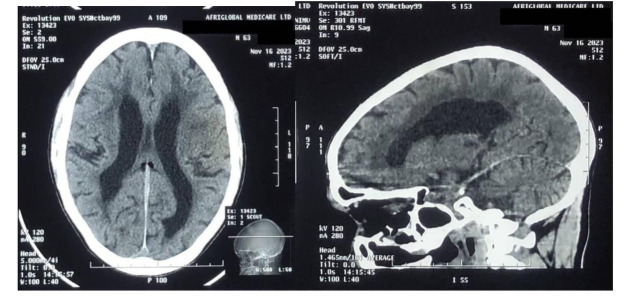

Results: The patient's symptoms, including insidious gait difficulties, speech impairment, and memory loss, led to a suspected diagnosis of NPH. However, the sudden improvement of neurological deficits indicated a vascular cause. Computed Tomography (CT) imaging identified supporting evidence of a lacunar stroke, leading to a revised diagnosis.